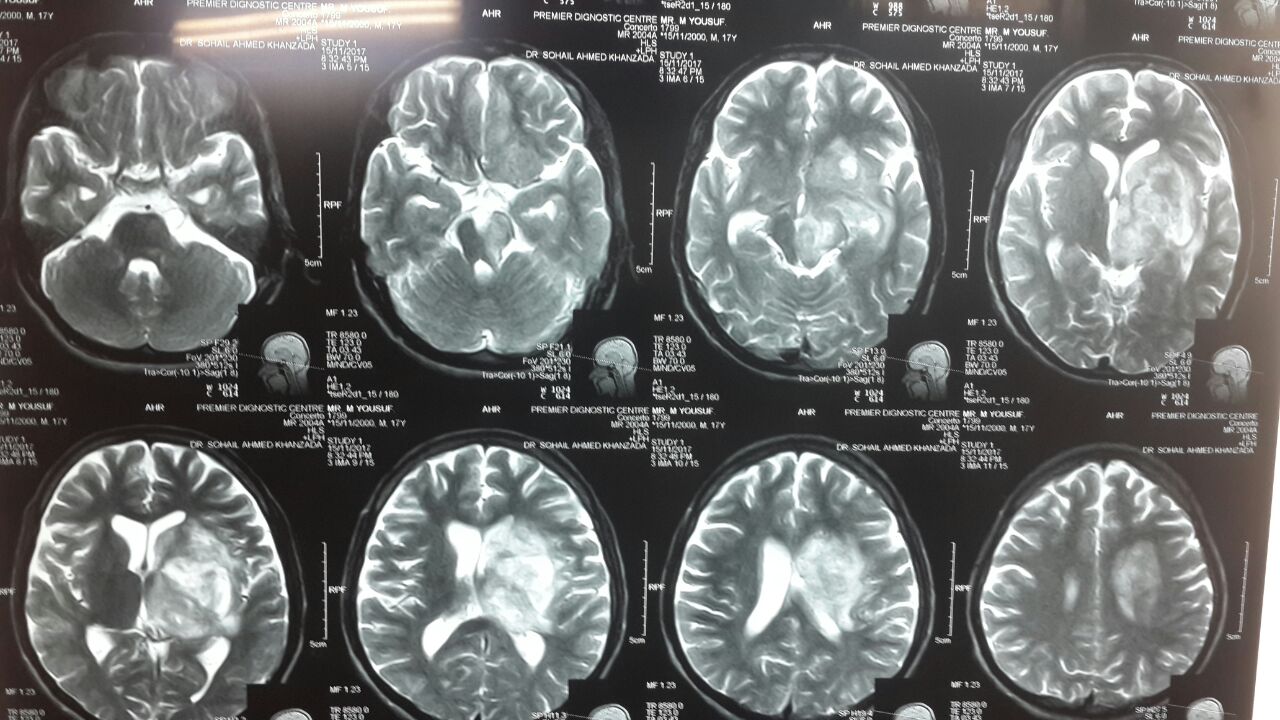

Case#151

17 years old..

Hx of high grade fever 7 days back

Pt consious. .Aphasic.

6th and 7th nerve palsy

Rt side hemiplegia. .